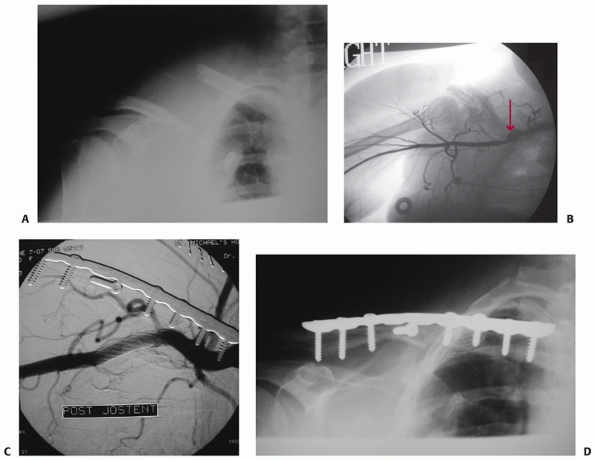

vehicular trauma are more likely to have associated injures to the

hemothoraces/pneumothoraces28,89,162 (Fig. 36-6).

primary fixation (Fig. 36-7). The clavicle can also be injured from penetrating trauma including projectiles, blasts, and sword or machete blows (Fig. 36-8).

![]()  |

|

FIGURE 36-6

Anteroposterior radiograph of the clavicle in a 42-year-old man involved in a motor-vehicle collision. Associated injuries include multiple ipsilateral upper rib fractures, an ipsilateral pneumothorax (arrows outlining collapsed lung), and multiple lower extremity fractures. This patient has four relative indications for operative fixation: (i) the severe displacement of the clavicle fracture, (ii) the multiple upper rib fractures, which tend to destabilize the shoulder girdle, (iii) the associated lower extremity fractures and the resultant need for immediate upper extremity use, and (iv) the pneumothorax, which is indicative of the degree of trauma applied to the shoulder.  |